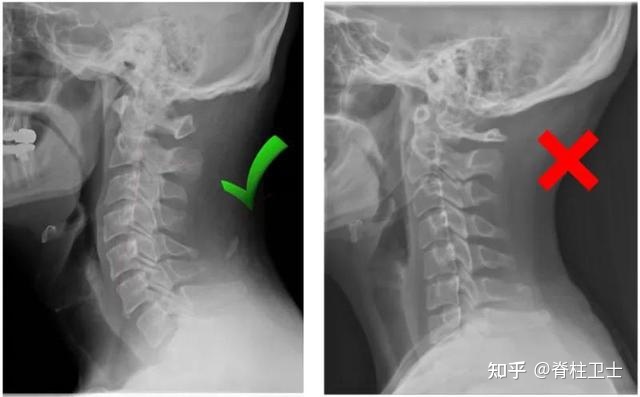

02_拍X片

到医院拍个X片,能比较直观地看到颈椎曲度的变化。